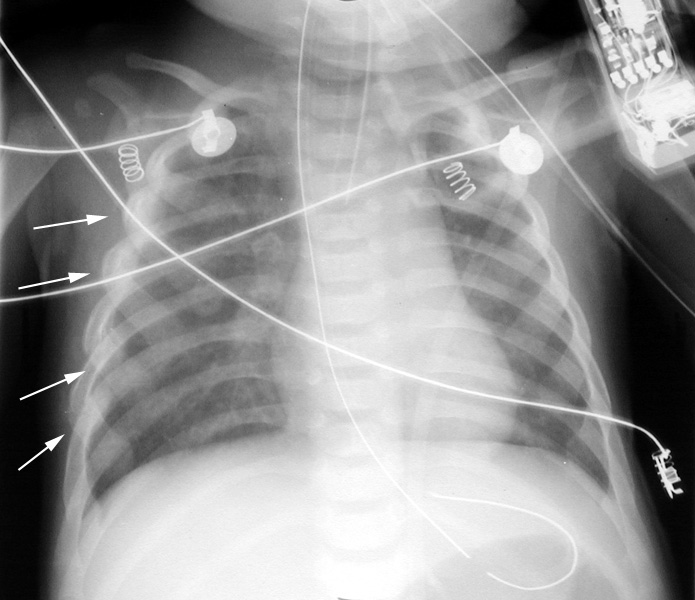

Rib films: multiple posterior rib fractures with callus